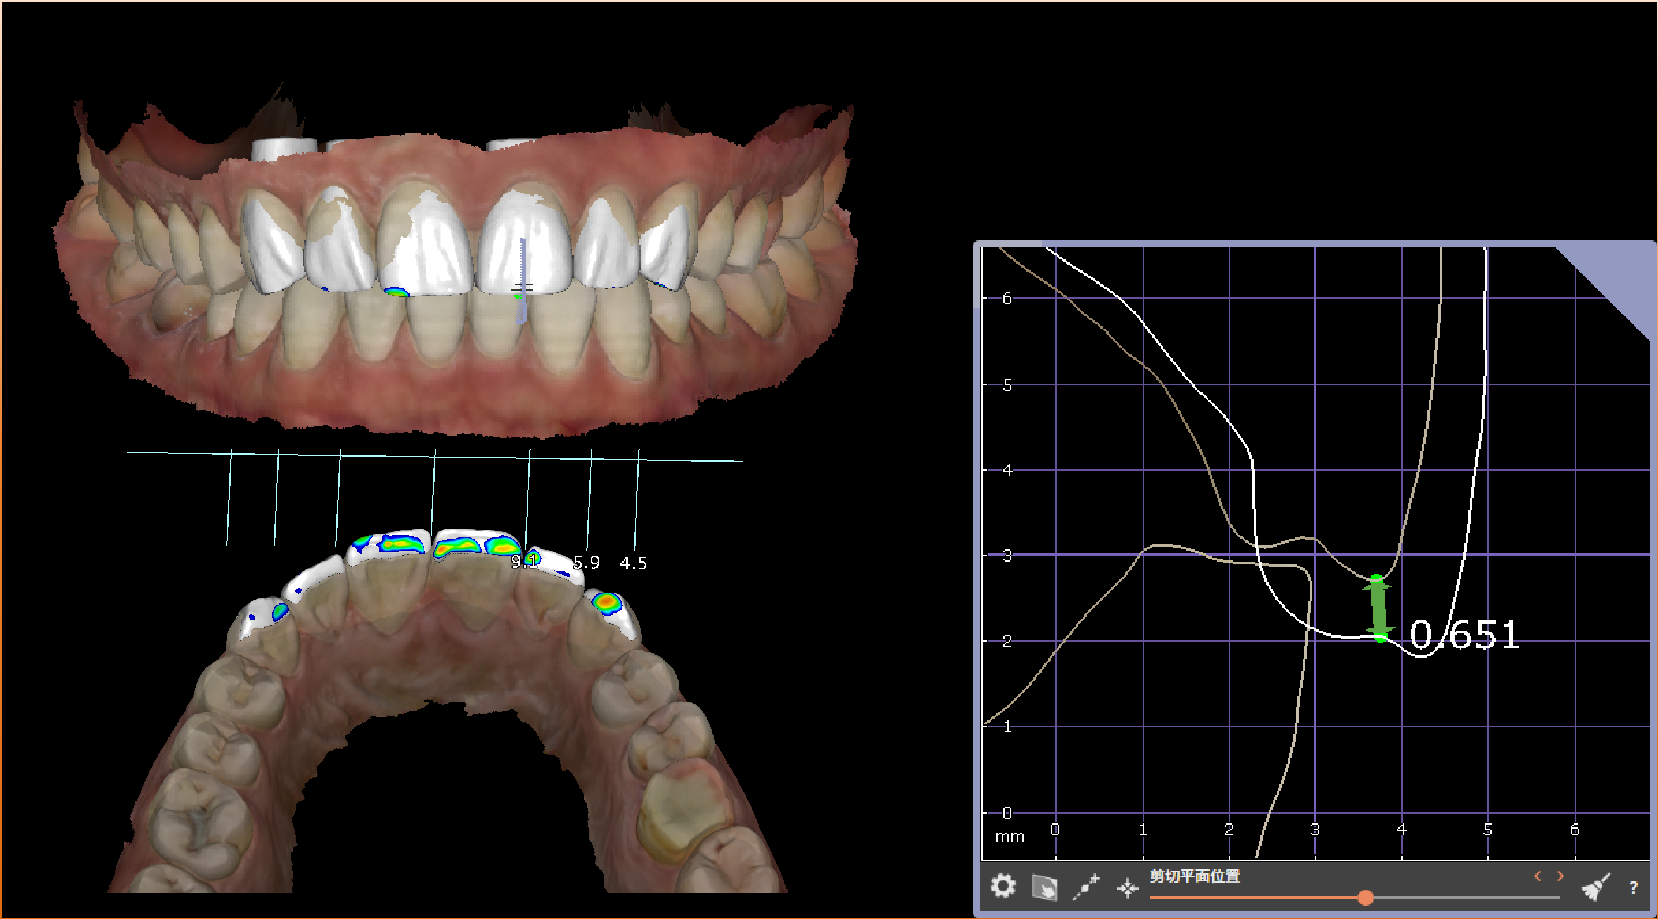

真实案例

TRUE CASE